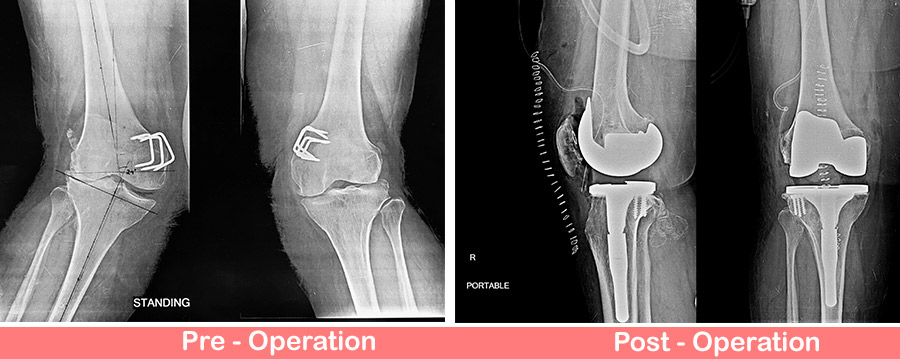

60 years old lady came with complaints of pain in both knees and valgus deformity. She had past history of operation around both knees in her childhood for deformity correction. Pre-op x-rays shows arthritic knee with severe valgus deformities. Thus she planned for Total Knee Replacement staged wise due to obesity and diabetes. This procedure requires special planning and implants.

Patient underwent Right Total Knee Replacement with stem tibial component, augmentation of tibial defects with screws and patella resurfacing.

Now patient is comfortable and walking with walker.